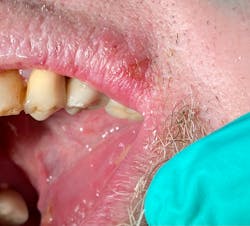

When we sat the patient back in the chair for delivery of local anesthetic, numerous large, irregular-bordered ulcerated lesions were noted throughout theUpon inquiring, the patient stated that since his tooth broke, his tongue perpetually rubbed against the flipper, eventually causing those lesions, as well as others, throughout his mouth. He said the lesions appeared about one week prior. Given the location and duration of the lesions and the patient’s health history, it was clear that the partial was not the genesis for this pathology; stress and poor health were indeed the culprits.

Well, the ramifications of COVID-19 once again have reared their ugly head. Stress, grinding, increased blood pressure, nervous habits, poor diet, diagnosis of type 2 diabetes...put all of these into a melting pot of challenges that place strain on the body’s systems, and something has to give. In this particular scenario—due to the size and conglomerated nature of the lesions—the patient had herpetiform/aphthous major ulcers.